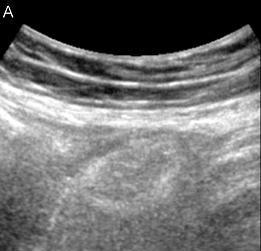

Een 21-jarige vrouw kwam op de Spoedeisende Hulp met pijn rechts onderin de buik, diarree en misselijkheid. De buikpijn bestond sinds 5 dagen en was acuut ontstaan. Haar medische voorgeschiedenis was blanco, behoudens een chirurgisch gecorrigeerd congenitaal hartdefect. Patiënte had geen koorts en bij lichamelijk onderzoek geen défense musculaire of loslaatpijn. Laboratoriumonderzoek toonde geen afwijkende infectieparameters. Een echografie van het abdomen toonde rechts in de onderbuik een niet-comprimeerbare, hypo-echogene, ovale afwijking.